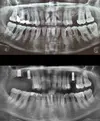

Implant tedavisi

Periimplantitis

Peri-İmplant Mukozitis